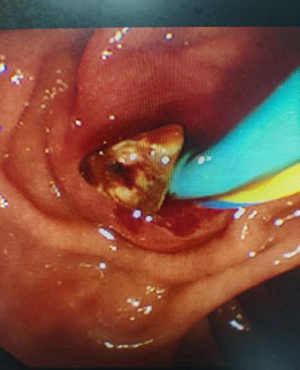

图片15

取出结石